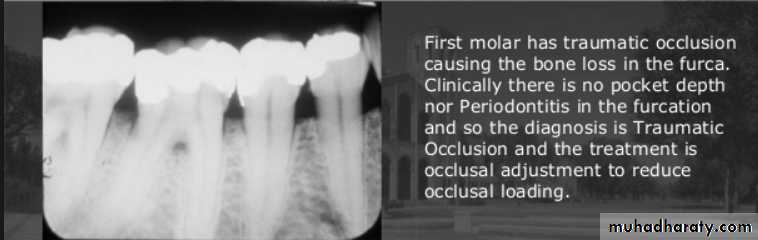

Clinical symptoms of traumatic occlusion

Excessive wear of teethMobility, tooth migration,

Pain during and after occlusal contact.

Muscle spasm,& joint symptoms.

Radiographic findings

Widening of periodontal space with either thickening or loss of lamina dura

Periapical or Furcation radiolucency

Resorption of alveolar bone

Root resorption